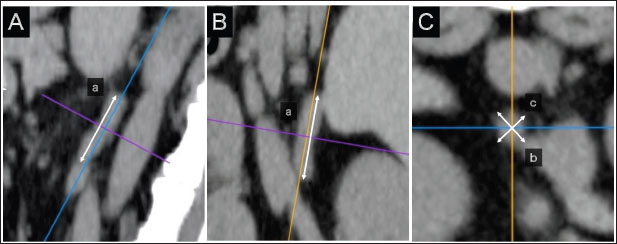

The spinal cavity of T13–L5, which is close to the bilateral adrenal glands, was selected as a candidate for the reference site. The T13–L5 spinal cavity was measured on 3D-MPR from CT images using the bone algorithm (window level: 300, window width: 1,500). In the sagittal and dorsal planes, the crosshairs were adjusted so they were parallel to the spinal cord. In the sagittal sections, the plane passing through the center of the dorsal edge of each vertebral body was drawn in the transverse plane (Fig. 2A–C). The height of the spinal cavity visualized in the cross-plane was recorded (Fig. 2Ca).

Fig. 2. Method used for measuring the height and width of the L2 spinal cavity. In the sagittal (A) and dorsal (B) sections, the crosshairs were adjusted to be parallel to the spine. In the sagittal section (A), a line passing through the center of the dorsal edge of the L2 vertebral body is depicted in the transverse section (C). The spinal cavity height (a) depicted in the transverse section (C) was measured.